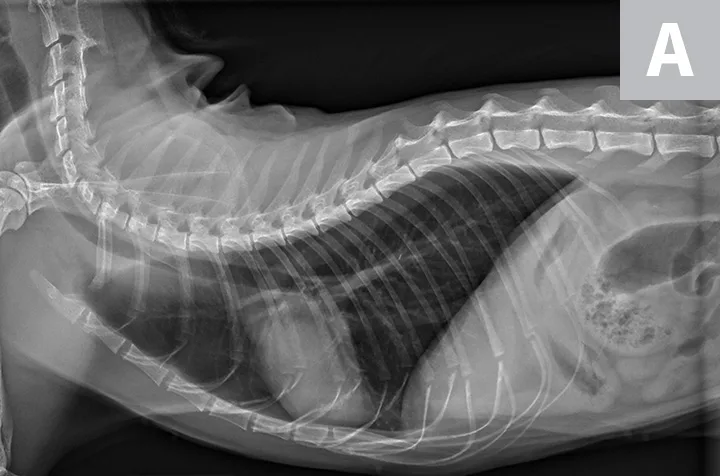

Thoracic radiographs are generally difficult to assess in cats due to age-associated variability. The cardiac silhouette develops increased sternal contact as cats age (Figure 1), with the aorta creating a notch or right-angled appearance that can falsely suggest left atrial enlargement on ventrodorsal projection. The aortic arch may have a rounded appearance on the ventrodorsal projection that can be mistaken for a pulmonary nodule in the left cranial lung lobe (Figure 2).1

FIGURE 1A

Lateral radiographs of a 2-year-old cat (A) and a 9-year-old cat with increased sternal contact of the cardiac silhouette (B).